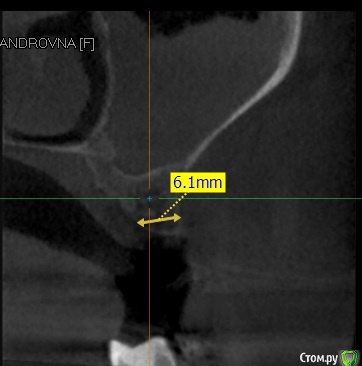

alboard Опубликовано 7 ноября, 2015 Поделиться Опубликовано 7 ноября, 2015 Пациентке удалили 26 зуб в феврале 2015. Делали кт через месяц по поводу другого зуба, в пазухе проблем не было. Ортодонтическое лечение близится к завершению, сделали на днях повторное КТ. И на нем такая картина. Санация пазухи? Если не сложно, подскажите специалиста в личку. Ссылка на комментарий

red_butler Опубликовано 7 ноября, 2015 Поделиться Опубликовано 7 ноября, 2015 На Кт видно соустье? Ссылка на комментарий

alboard Опубликовано 7 ноября, 2015 Автор Поделиться Опубликовано 7 ноября, 2015 К сожалению, нет. Ссылка на комментарий

IvanK Опубликовано 7 ноября, 2015 Поделиться Опубликовано 7 ноября, 2015 К сожалению, нет.а посмотреть хочется)) 1 Ссылка на комментарий